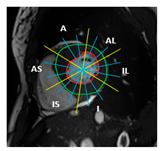

| Section | Segmented Cine-MRI | 17-Segment Model | Proposed 49-Sub-Segment Model | Number of Misclassifications |

| Basal section | ![]() | ![]() | ![]() | 9 sub-segments (2 sub-segments of segment 1 + 3 sub-segments of segment 2 + 3 sub-segments of segment 3 + 1 sub-segment of segment 5) |